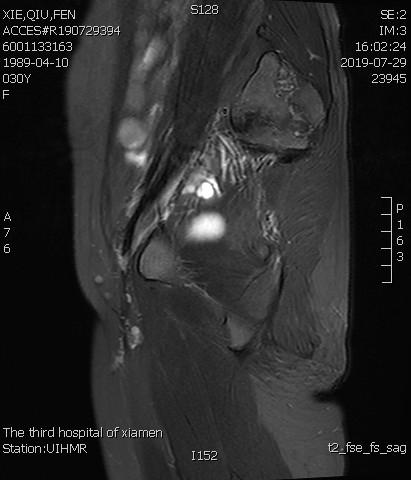

- 患者术后1个月痛经明显缓解。术后3个月复查MRI显示子宫明显缩小,前壁病灶萎缩坏死。

术后3个月复查MRI显示子宫明显缩小,前壁病灶萎缩坏死